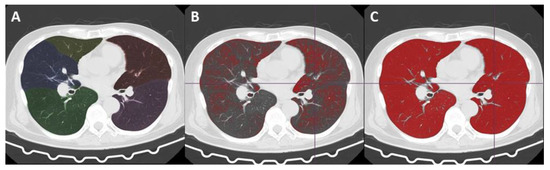

Automated Volume Analysis of the CT Images